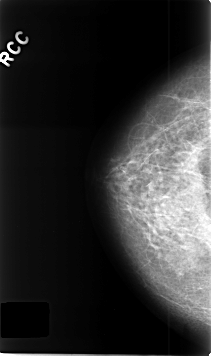

Volume: benign_06 Case: C-0389-1

C_0389_1.RIGHT_CC

RIGHT_CC LINES 4616 PIXELS_PER_LINE 2736 BITS_PER_PIXEL 12 RESOLUTION 50 NON_OVERLAY

RIGHT_MLO LINES 4544 PIXELS_PER_LINE 2736 BITS_PER_PIXEL 12 RESOLUTION 50 NON_OVERLAY